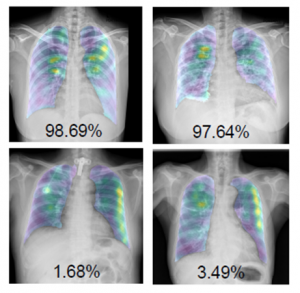

The “COVID-19 detection and heatmap generation in chest x-ray images” proposed an alternative solution, using image processing technology and deep learning to assist in automatically detecting COVID-19 from chest x-ray images. The models are trained to classify chest x-ray images into three classes including normal, COVID-19, and other viral and bacterial diseases, as well as show heatmaps with their confidence scores of being COVID-19, which can help conclude the final diagnosis.